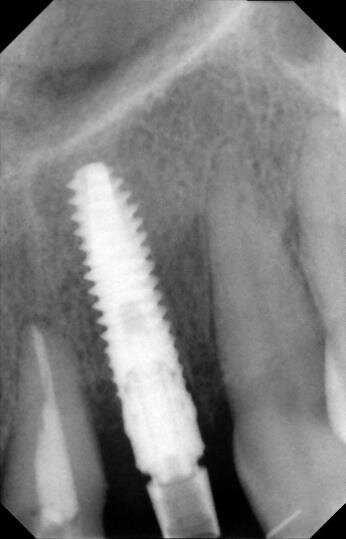

La fase chirurgica viene pianificata con la preparazione iniziale (igiene orale, controllo emato-chimico delle condizioni della paziente, prescrizione della profilassi/terapia antibiotica19-20 e della sospensione del fumo). Il 23 giugno 2011, vengono estratti i due incisivi laterali (Figg. 13, 14) e inseriti contestualmente due impianti Xive (Dentsply) di diametro 3,8 mm e lunghezza 15 mm (Figg. 15, 16), dimensioni ottimali per la successiva protesi (ponte di 4 elementi da 1.2 a 2.2 con 1.1 e 2.1, elementi “intermedi”).

Vengono inserite due viti di guarigione e riposizionato il provvisorio, debitamente adattato in corrispondenza dei due incisivi laterali. Alla seduta di controllo a una settimana dall’intervento implantare, la paziente confida, alle assistenti dello studio, di non aver assunto gli antibiotici prescritti né prima né dopo l’inserimento degli impianti e tantomeno di essersi astenuta o limitata dal fumo di sigarette! Alla seconda visita di controllo, dopo 30 giorni, la stessa presenta un pessimo stato di igiene orale e due ascessi vestibolarmente ai due impianti (1.2 e 2.2) (Figg. 17, 18).